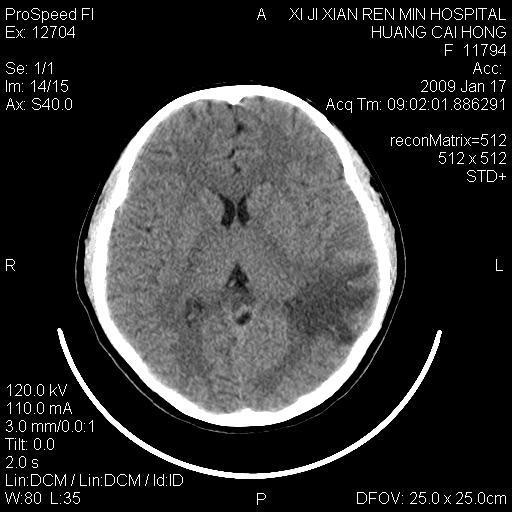

以下是引用zbp537在2009-1-19 13:54:00的发言:[br]首先考虑脑炎。[br]诊断依据:[br]1、患者较年轻。[br]2、有感冒病史。[br]3、左侧颞枕叶这么大一片低密度影,占位征象却不明显,不符合肿瘤特征,其内的高密度影为出血灶。

以下是引用xiaoniu在2009-1-19 13:29:00的发言:[br]左侧颞叶三角形低密度影,占位效应不明显,其内点片样高密都影,青少年患者,首先考虑:少突胶质瘤。因为有感冒病史,不能除外感染的可能。